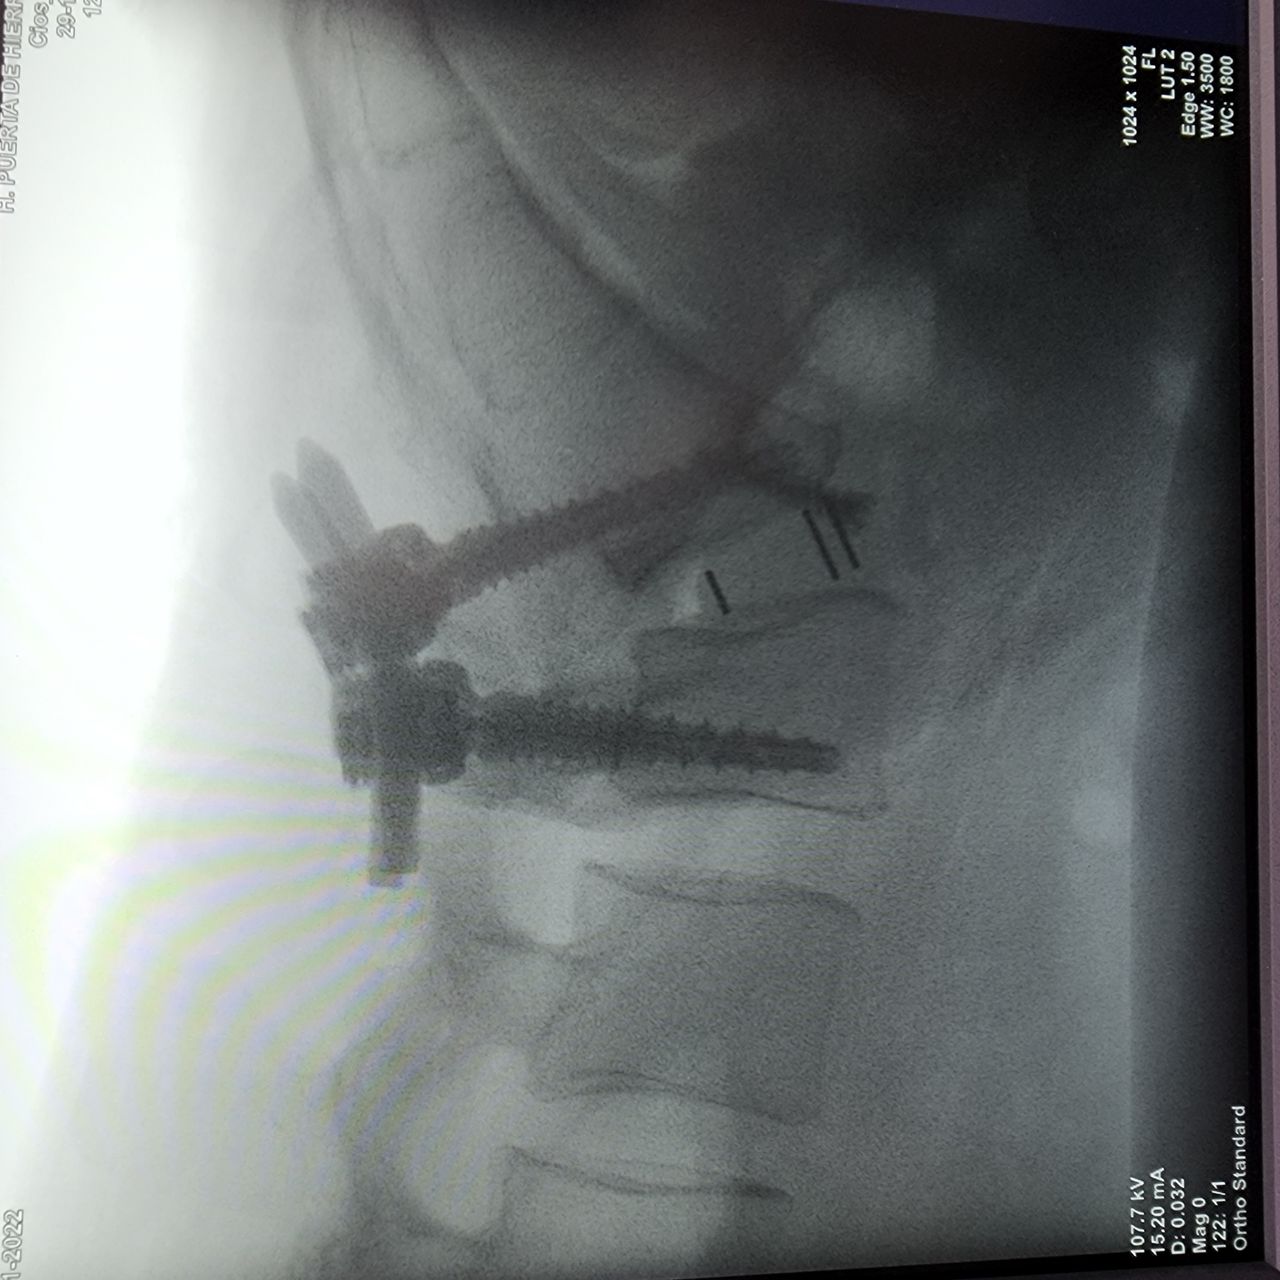

• Alta Especialidad En Cirugía De Columna Vertebral-Privado-San Juan Del Río, Qro 2019-2020.

Presento una Alta Especialidad en Cirugía de Columna Vertebral, con la cual brindo atención para resolver enfermedades como hernias discales, espondilolistesis, tumores óseos vertebrales, fracturas vertebrales, desgaste articular vertebral, deformidades de la alineación de columna vertebral y enfermedades asociadas a nervios en los diferentes segmentos vertebrales.

Cirugía Mínima Invasión de Columna Vertebral

Cirugía Anterior para Fusión Columna Vertebral Lumbar

Cirugía de Fusión para Columna Cervical

Cirugía de cifoplastía, vertebroplastía en caso de fracturas vertebrales.

Cirugía para deformidades de Columna Toraco Lumbar.